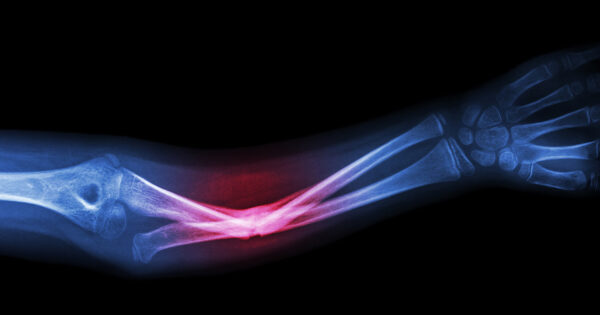

อาการกระดูกหัก

อาการกระดูกหักมักเห็นชัดเจนจะบวมปวด ไม่สามารถลงน้ำหนักหรือเคลื่อนไหวได้บริเวณที่หัก โดยเฉพาะกระดูกสะโพกหักในผู้สูงอายุจะมีอัตราเสี่ยงสูงต่อการเสียชีวิตจากภาวะแทรกซ้อน ดังนั้นจึงควรตรวจวัดความหนาแน่นของมวลกระดูกทุกปี เพื่อป้องกันกระดูกทรุดตัว เสริมความแข็งแรงด้วยการออกกำลังกาย ทานอาหารแคลเซียมสูงตั้งแต่อายุยังน้อย